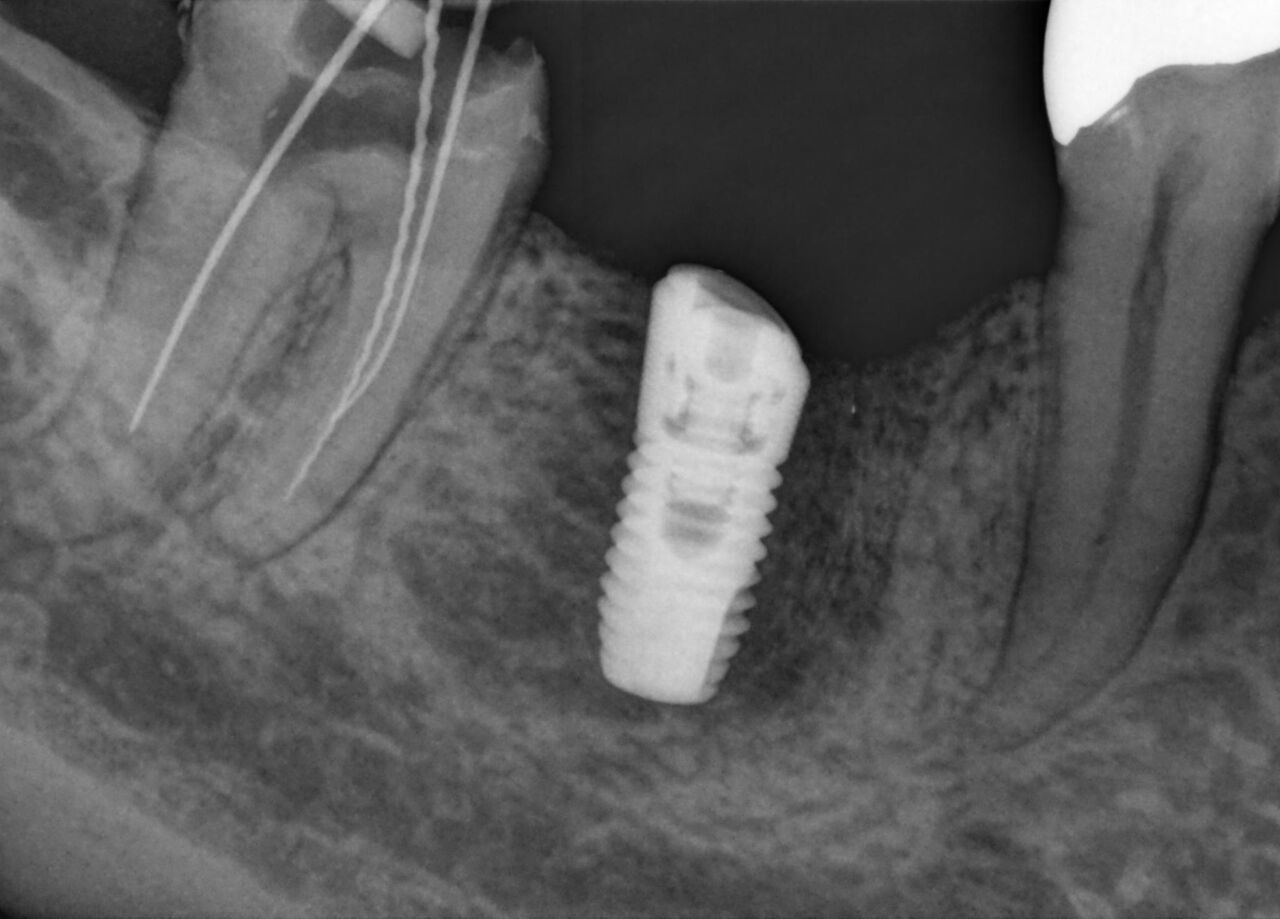

Imágenes superiores para cuidado óptimo del paciente

Los sensores intraorales de Dentsply Sirona proporcionan calidad de imagen de vanguardia que apoya el diagnóstico preciso del tratamiento y visión clara de la situación clínica. Respaldado por elecciones expansivas del sistema, mejora de filtro de imagen y servicio de vanguardia y personal de apoyo, los sensores intraorales Xios ofrecen varias posibilidades para su consultorio - brindándole beneficio a usted y sus pacientes.